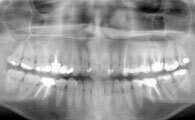

Le traitement orthodontique peut être effectué sur les dents de lait, ou en denture mixte si les dents de lait cohabitent avec des dents définitives.